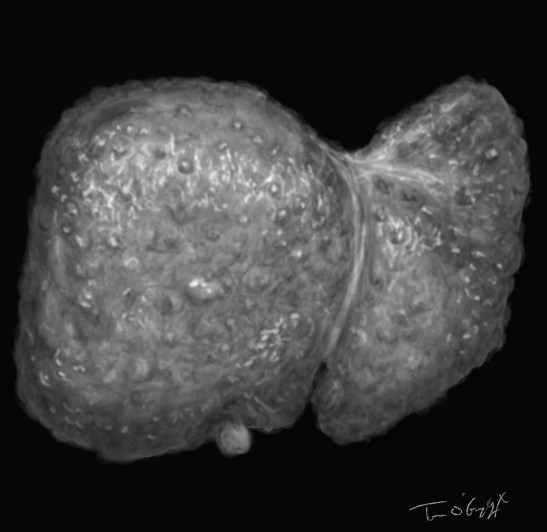

cirrhose hepatique micronodulaire

cirrhose micronodulaire alcoolique sur foie prélevé par autopsie